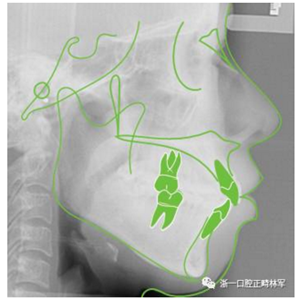

治療前側(cè)位片

5.png

頭影測量分析

Ricketts分析

6.png